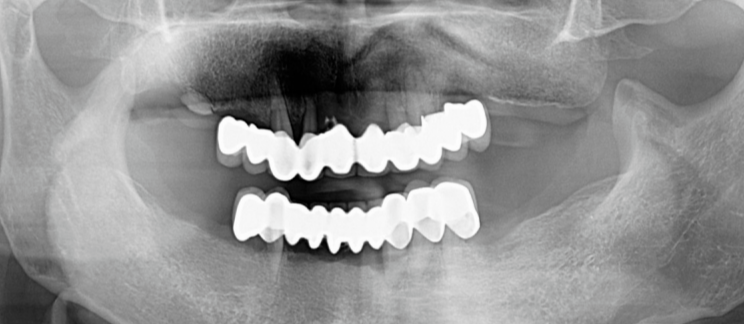

30 年后,她的上颌只剩下最后 3 颗牙齿是自己的,其他都是假牙。对比惨不忍睹的上颌,她的下颌牙齿都还完好,仅有一些磨损和轻微的松动。

在数字化辅助设计和手术导航下,种植科医生给她完成了半口种植牙的精准种植,一期手术植入 6 颗种植体。

期间,修复科医生还为她制作了美观实用的活动义齿作为过渡,避免了无牙期的尴尬和不便。种植二期术后,顺利完成了最终的马龙桥+全瓷冠(种植固定义齿)修复。